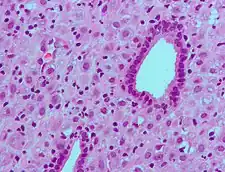

Metabolism

The metabolism of progesterone is rapid and extensive and occurs mainly in the liver,[112][113][114] though enzymes that metabolize progesterone are also expressed widely in the brain, skin, and various other extrahepatic tissues.[77][115] Progesterone has an elimination half-life of only approximately 5 minutes in circulation.[112] The metabolism of progesterone is complex, and it may form as many as 35 different unconjugated metabolites when it is ingested orally.[114][116] Progesterone is highly susceptible to enzymatic reduction via reductases and hydroxysteroid dehydrogenases due to its double bond (between the C4 and C5 positions) and its two ketones (at the C3 and C20 positions).[114]

The major metabolic pathway of progesterone is reduction by 5α-reductase[77] and 5β-reductase into the dihydrogenated 5α-dihydroprogesterone and 5β-dihydroprogesterone, respectively.[113][114][117][118] This is followed by the further reduction of these metabolites via 3α-hydroxysteroid dehydrogenase and 3β-hydroxysteroid dehydrogenase into the tetrahydrogenated allopregnanolone, pregnanolone, isopregnanolone, and epipregnanolone.[119][113][114][117] Subsequently, 20α-hydroxysteroid dehydrogenase and 20β-hydroxysteroid dehydrogenase reduce these metabolites to form the corresponding hexahydrogenated pregnanediols (eight different isomers in total),[113][118] which are then conjugated via glucuronidation and/or sulfation, released from the liver into circulation, and excreted by the kidneys into the urine.[112][114] The major metabolite of progesterone in the urine is the 3α,5β,20α isomer of pregnanediol glucuronide, which has been found to constitute 15 to 30% of an injection of progesterone.[17][120] Other metabolites of progesterone formed by the enzymes in this pathway include 3α-dihydroprogesterone, 3β-dihydroprogesterone, 20α-dihydroprogesterone, and 20β-dihydroprogesterone, as well as various combination products of the enzymes aside from those already mentioned.[17][114][120][121] Progesterone can also first be hydroxylated (see below) and then reduced.[114] Endogenous progesterone is metabolized approximately 50% into 5α-dihydroprogesterone in the corpus luteum, 35% into 3β-dihydroprogesterone in the liver, and 10% into 20α-dihydroprogesterone.[122]

Relatively small portions of progesterone are hydroxylated via 17α-hydroxylase (CYP17A1) and 21-hydroxylase (CYP21A2) into 17α-hydroxyprogesterone and 11-deoxycorticosterone (21-hydroxyprogesterone), respectively,[116] and pregnanetriols are formed secondarily to 17α-hydroxylation.[123][124] Even smaller amounts of progesterone may be also hydroxylated via 11β-hydroxylase (CYP11B1) and to a lesser extent via aldosterone synthase (CYP11B2) into 11β-hydroxyprogesterone.[125][126][44] In addition, progesterone can be hydroxylated in the liver by other cytochrome P450 enzymes which are not steroid-specific.[127] 6β-Hydroxylation, which is catalyzed mainly by CYP3A4, is the major transformation, and is responsible for approximately 70% of cytochrome P450-mediated progesterone metabolism.[127] Other routes include 6α-, 16α-, and 16β-hydroxylation.[114] However, treatment of women with ketoconazole, a strong CYP3A4 inhibitor, had minimal effects on progesterone levels, producing only a slight and non-significant increase, and this suggests that cytochrome P450 enzymes play only a small role in progesterone metabolism.[128]